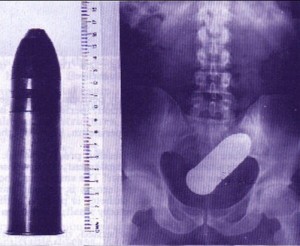

ტყვია

1 (1)